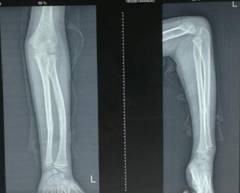

西医手术先进全面:运用DCO理念,阶梯序贯抢救及治疗严重骨盆骨折、多发性、开放性重大骨折创伤;常规开展复杂骨盆髋臼骨折、手足显微外科的手术治疗;以最先进的生物学固定理念为指导,运用微创手术技术治疗骨折,包括:四肢长骨骨折的交锁髓内固定技术、MIPPO(微创经皮钢板内固定技术)、股骨近端骨折髓内固定技术(PFNA)、外固定支架固定技术等等均达国内先进水平。

中医骨伤特色明显:包括特色复位手法、传统夹板传承并革新;中药经验方药内服、外敷及离子导入疗法、中药水浴、熏蒸以及骨折后康复治疗等等可有效促进骨折愈合、治疗骨不连;吊兜悬吊牵引结合功能锻炼保守胸腰椎压缩性骨折;骨髓炎广泛开窗换药+外固定支架技术、感染骨段切除骨延长技术治疗,结合中医药辩证治疗等。

微创治疗肱骨干骨折

优点:闭合复位,不干扰骨折断端,中心固定,利于愈合。

徐州市中医院骨伤科在注重中医传统治疗的同时,兼顾手术的发展,在外科手术微创化的时代,中医院骨伤科也走出特色的微创之路。关节科开展关节镜下微创肩袖撕裂修补,冻结肩松解,肩关节撞击症肩峰下减压术,膝关节交叉韧带损伤重建,半月板损伤修补等手术,避免大切口、大创伤、恢复快。脊柱科采用椎间孔镜等脊柱微创手段实施各种脊柱微创手术。UBE技术(单边双通道内镜下的脊柱手术及微创镜下融合技术)、脊柱内镜下ULBD技术(单侧椎板入路双侧椎管减压手术及微创镜下融合技术)及MI-PCF技术(Key-hole技术,内镜下颈椎后路椎间孔开孔)。创伤科运用微创手术技术治疗骨折,包括:四肢长骨骨折的交锁髓内固定技术、MIPPO(微创经皮钢板内固定技术)、股骨近端骨折髓内固定技术(PFNA)、外固定支架固定技术等等均达国内先进水平。